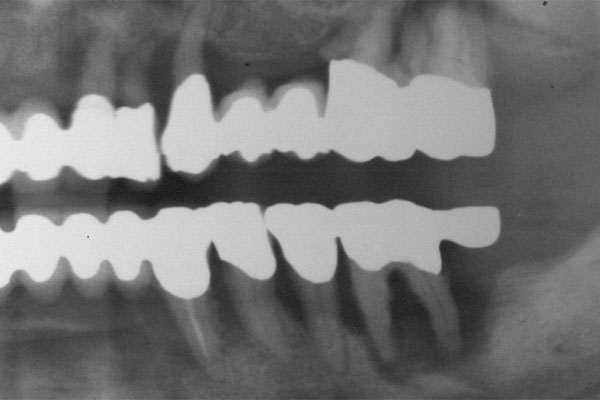

So vielfältig die Ursachen so weitreichend muss die Planung für die Implantologie sein. Alle Disziplinen der Zahnheilkunde sowie allgemeinmedizinische Aspekte sind zu betrachten. Ursachen (Nichtanlage, Unfall, Karies und Parodontitis)

Karies

Parodontitis